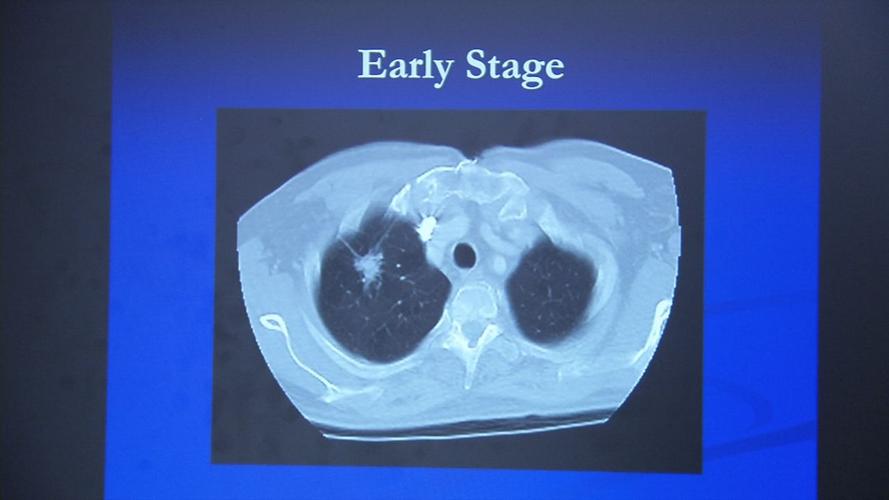

The early diagnosis rate in Kentucky, 18.8%, also falls below the average rate of 21.5%.

The state's five-year lung cancer survival rate is only 17.6%, which ranks 41st among the 45 states with survival data. The national five-year survival rate is 21.7%.